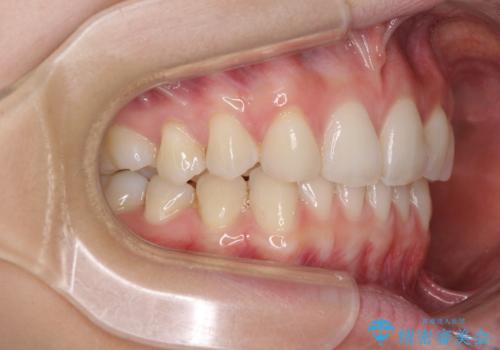

上顎前歯が2本欠損 インビザラインによる叢生の解消

- 深い咬み合わせと前歯のデコボコを気にして来院された患者様です。

上顎前歯2本が欠損しているため、妥協的なゴールを設定しインビザラインで矯正治療を行うこととしました。

上下前歯の大きさのアンバランスにより、深い咬み合わせと奥歯の咬みにくさがなかなか解決されず、治療に長期間を要することとなりました。